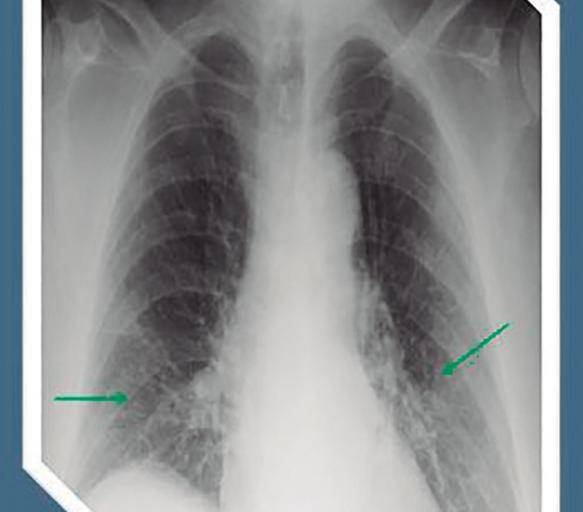

En el caso de las enfermedades respiratorias, la información disponible indica que también las personas asintomáticas, las que no tienen o tuvieron síntomas muy graves y aquellas que no fueron hospitalizadas presentan porcentajes de fibrosis en los pulmones.

“Eso definitivamente deja un órgano disfuncional y muchas personas han tenido que reaprender a respirar para aprovechar ese 50 por ciento de pulmón que les queda. Eso es una condición incapacitante”.

Pérdida de cabello, erupciones cutáneas, cansancio, dolores de cabeza, depresión, ansiedad, cambios de humor, desregulación del sueño, disfunción olfativa y gustativa, cognición alterada, deterioro de la memoria, anomalías de la función pulmonar como la fibrosis, inflamación del miocardio, disfunción ventricular y lesiones renales agudas son ejemplos de secuelas cada vez más ligadas al coronavirus.